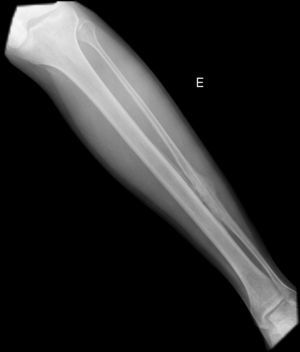

Clinical presentationA 42-year-old male with no prior history presented 3 months prior to his coming to our department with continuous pain in the middle third of the left leg. Upon examination there was selective pain on palpation on the mid third of the left tibia. No skin atrophy or deformity of the affected limb was detected. Laboratory analysis, including acute phase reactants, complete blood count, blood chemistry, bone remodeling markers in blood and urine, thyroid hormone and proteins, were normal. A simple X-ray of the left leg (Fig. 1) presented an image of hyperostosis with a thickened cortex on the mid third of the tibia and peroneus, extending along the bone and showing a “dripping candlewax” image. A bone scan with 99Tc (Fig. 2) observed an increase in uptake. A computerized tomography (Fig. 3a and b), showed dense cortical hyperostosis of the distal half of the tibial and peroneal diaphysis, with wavy and exhuberant borders, cortical sclerosis and periostic and endostic thickening, predominantly on the lateral tibia and mid peroneal, with a “dripping candlewax” aspect, suggestive of melorheostosis.